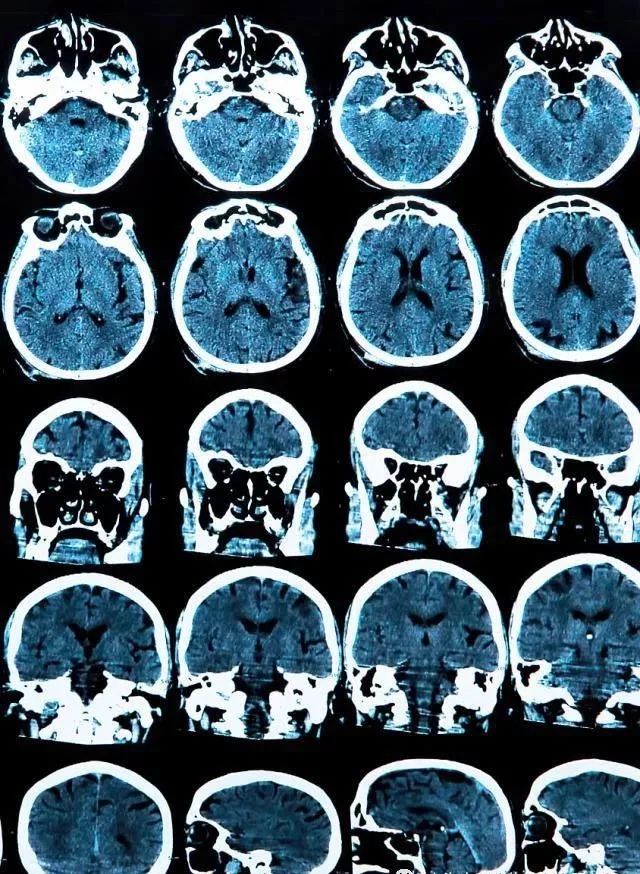

2019年,杂志Cell Transplant报道了一项移植干细胞治疗案例,8名帕金森病人通过细胞治疗严重的神经功能损伤,其中7名病人通过长达1年随访证实,整个干预过程安全有效,无免疫排斥反应,无严重副作用。 干细胞干预1年后,7名病人显示出均有不同程度运动功能改善,5名病人对现有干预具有更好响应,PET成像表明中脑多巴胺能神经元活性增强,病情改善比干预前效果显著。